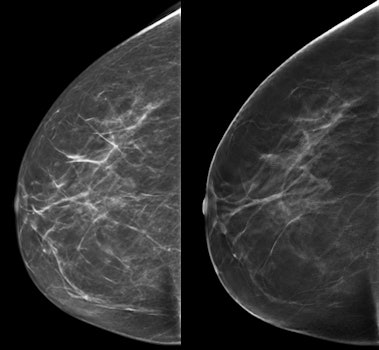

DBT vs. mammography

Radiologists are constantly seeking ways to improve breast cancer detection. Could DBT be the answer?

Some studies examining DBT add in 2D digital mammography, which raises the radiation dose for patients. Could DBT plus synthesized 2D mammography replace digital mammography altogether? And what does using DBT plus synthesized 2D mammography do to reading times and recall rates? That's precisely what Aase, Hofvind, and colleagues sought to discover.